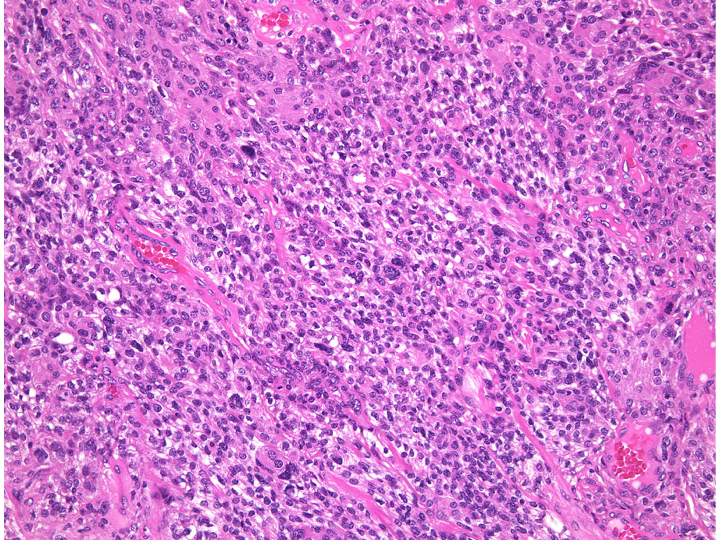

necrosis 壊死・atypical meningioma WHO grade 2 非定型髄膜腫

WHO grade 2 atypical meningioma (MIB-1 15%)に認められた壊死像です。この病理部分像からはgrade 2ですが,MIB-1も非常に高率です。さらに,多少なりとも核異型がみられるとgrade 3のanaplastic meningiomaになります。

anaplastic meningioma WHO grade 3 退形成性髄膜種

極めて高い細胞密度です。MIB-1は20%に達します。肉腫 sarcoma としての性質を有し,頭蓋内で転移し,摘出しても多発再発します。放射線外科治療でもコントロールすることはできません。